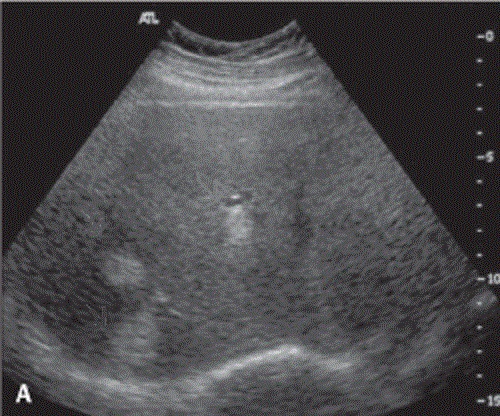

Kyste multiple simple du foie

droit . Le kyste inferieure est en vue tres nette

avec encloisonne